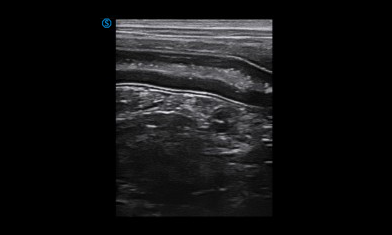

VP2 provides various applications for veterinary diagnosis with micro convex probe and linear probe.

Intestine